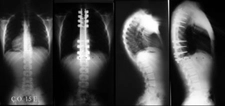

Her bir tür, farklı tedavi yaklaşımları gerektirebilir. İdiyopatik skolyoz, genellikle ergenlik döneminde ortaya çıkar ve tedavi edilmediğinde ciddi sorunlara yol açabilir. Skolyozun TanısıSkolyozun tanısı genellikle fizik muayene ve görüntüleme yöntemleri ile konur. Doktor, hastanın duruşunu değerlendirir ve gerekirse röntgen çekimi yapar. Röntgen, omurganın eğilimini ve açılarını belirlemeye yardımcı olur. Skolyoz Tedavi YöntemleriSkolyoz tedavisinde kullanılan başlıca yöntemler şunlardır:

Fizik Tedavi ve Egzersiz: Fizik tedavi, skolyozun ilerlemesini durdurmak ve postürü düzeltmek için önemli bir rol oynar. Hastalara özel egzersiz programları uygulanır. Bu programlar, kas gücünü artırmayı ve esnekliği geliştirmeyi hedefler. Ortez Kullanımı: Ortezler, omurganın düzeltilmesine yardımcı olmak için kullanılan cihazlardır. Özellikle büyüme çağındaki çocuklar için etkili olabilir. Ortezlerin kullanım süresi, skolyozun şiddetine bağlı olarak değişir. Cerrahi Müdahale: Eğer skolyoz ilerliyorsa ve diğer tedavi yöntemleri yeterli olmuyorsa cerrahi müdahale gerekebilir. Cerrahi işlemler genellikle omurganın düzeltilmesi ve stabilizasyonunu hedefler. Bu tür bir müdahale, hastanın yaşına, genel sağlık durumuna ve skolyozun şiddetine göre planlanır. SonuçSkolyoz tedavisi, bireysel ihtiyaçlara göre özelleştirilmelidir. Tedavi yöntemleri arasında fizik tedavi, ortez kullanımı ve cerrahi müdahale gibi seçenekler bulunmaktadır. Erken tanı ve uygun tedavi, skolyozun yönetiminde kritik öneme sahiptir. Her birey için en uygun tedavi yönteminin belirlenmesi, uzman bir hekim tarafından yapılmalıdır. Ek BilgilerSkolyoz hastalarının takip edilmesi ve düzenli kontrollerin yapılması, tedavi sürecinin etkinliği açısından önemlidir. Ayrıca, skolyozun psikolojik etkileri de göz önünde bulundurulmalıdır. Hastaların duygusal destek alması, tedavi sürecini olumlu yönde etkileyebilir. Skolyoz ile ilgili daha fazla bilgi ve destek almak için uzman sağlık profesyonellerine başvurulması önerilmektedir. |